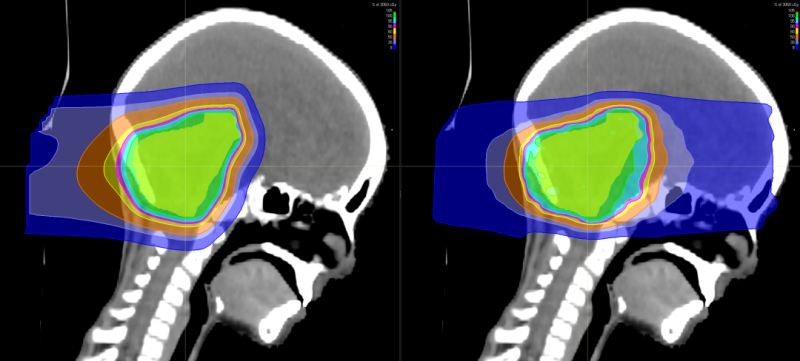

有研究表明,儿童神经母细胞瘤使用质子治疗的最大效益在于减少脑部正常组织构造的损伤,进而降低长期伤害。质子治疗是一种比其他任何形式的放射治疗更准确,更精确地靶向肿瘤,同时保留健康组织,目前全球最先进的一种放疗技术。通过质子治疗,可以最大限度地避免靶标外部的绝大多数不必要的辐射。

与传统形式的辐射相比,质子束会到达肿瘤内部的精准位置而不是沿着光束离开人体的路径释放大部分辐射剂量。实际上,质子没有肿瘤之外的辐射“退出剂量”,这意味着质子停在肿瘤上,不会继续伤害身体的健康部位。

随着儿童癌症治疗进步,儿童的存活率上升,存活下来的儿童患者日后之生活品质越来越受到关注,质子治疗具备能够减少散射剂量的优势,提升对肿瘤局部的控制,同时由于脑部神经组织多,易受辐射损害。质子治疗因具有布拉格峰的物理特性,使峰值部位对准肿瘤病灶处,发出最高剂量,产生最高峰,达到最佳杀瘤效果;峰后剂量趋于零,对周边脑组织几乎无影响。对于儿童脑瘤,可以避免有常规化疗引起的听力丧失、认知功能障碍、智力影响等。